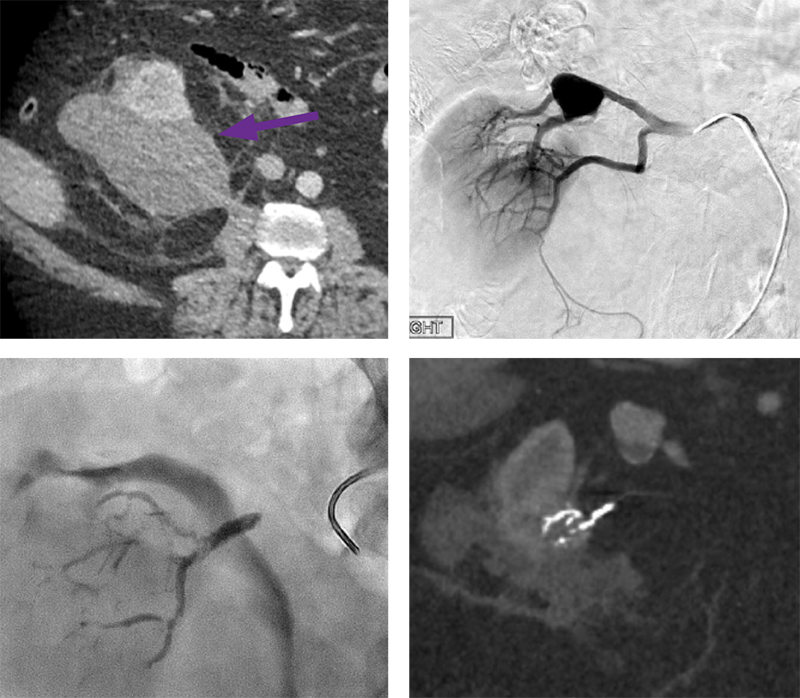

71-year-old male presented with acute onset right flank pain and was found to have a perinephric hematoma secondary to a ruptured complex right renal cyst.

The right femoral artery was accessed. An RDC catheter was utilized to catheterize the right renal artery and angiography was performed. A right renal mass arises from the inferior pole of the right kidney which is supplied by the lower pole renal artery. There is a pseudoaneurysm arising from the upper pole renal artery. There is no evidence of active hemorrhage.

A 2.8 F microcatheter/microwire tandem was advanced into the inferior pole renal artery. Arteriography demonstrates the renal mass arises from the inferior pole of the right kidney. 0.4 mL of Obsidio Embolic was injected through the microcatheter and follow-up arteriography demonstrates  complete stasis in the artery supplying the renal mass.

One-month post-procedure CT demonstrates decrease in size of subcapsular right perinephric hematoma and decrease in size of the renal artery aneurysm.

Scan images from Obsidio case.